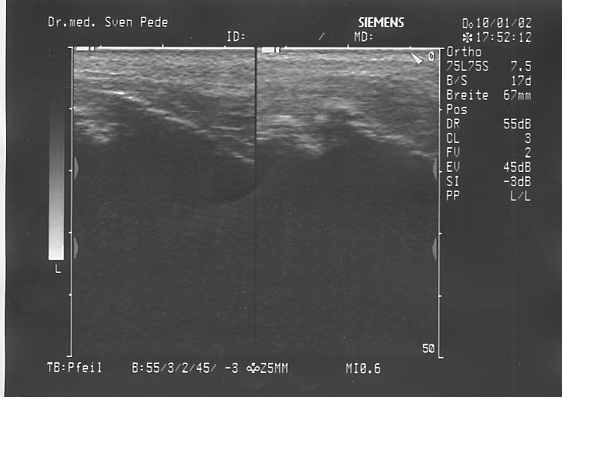

Morbus Osgood Schlatter

Bei dem Morbus Schlatter handelt es sich um eine Erkrankung, welche bei Jugendlichen im Alter zwischen 14 bis 16 Jahren abläuft. Es handelt sich um eine Verknöcherungsstörung des Ansatzbereiches der Kniescheibensehne am Schienbeinkopf. Der Ansatzbereich der Sehne verwächst nicht mit dem Schienbein, so daß hier ein isolierter Knochenkern bestehen bleibt.

Dies führt zu einer Verdickung, welche bei stärkerer sportlicher Belastung und insbesondere beim Knien schmerzhaft sein kann.

• SchlatterSONO3